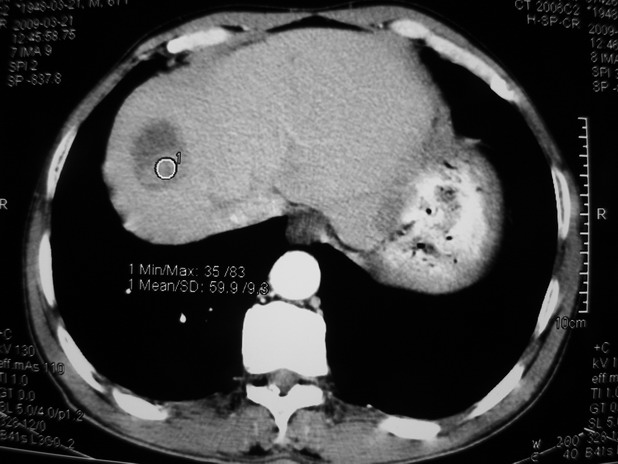

以下是引用余辉在2009-3-21 21:36:00的发言:[br]图像太乱了,建议楼主直接将强化数据按顺序列出来,病灶位置较表浅薄,有肝炎病史,灶内实性成分有显著强化,动脉期约60hu,考虑肝癌可能性大,进一步检查。